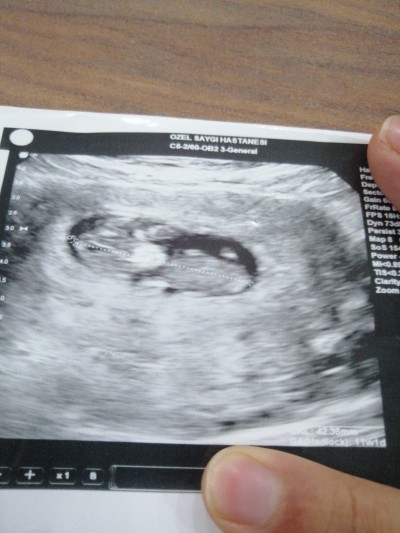

meraba hanimlar çok merak ediyorum sizce cinsiyeti bedir

11+1

Kesesine göre erkek